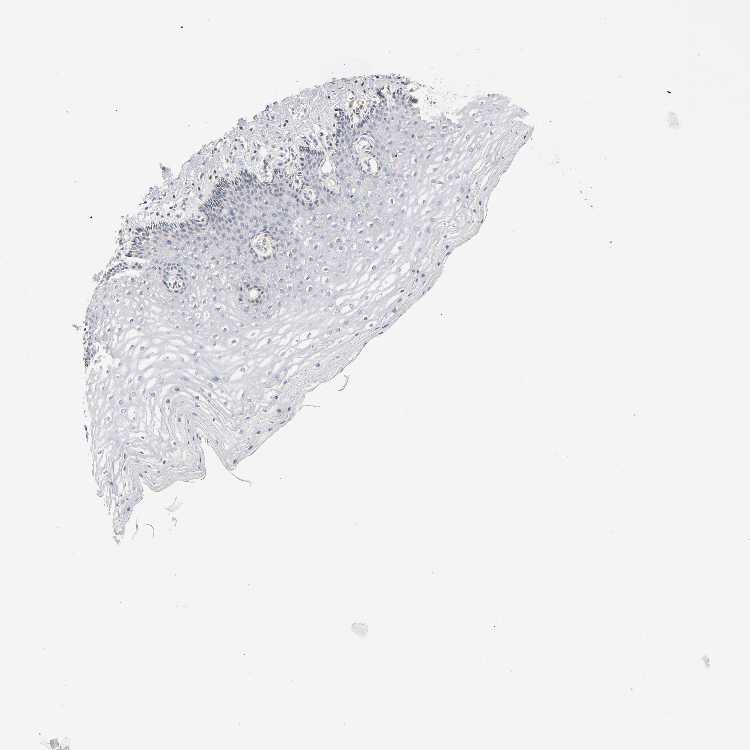

CERVIX - Antibody stainingi

Antibody staining in the annotated cell types in the current human tissue is reported as not detected, low, medium, or high, based on conventional immunohistochemistry profiling in selected tissues. This score is based on the combination of the staining intensity and fraction of stained cells.

Each image is clickable and will lead to virtual microscopy that enables deeper exploration of all samples and also displays staining intensity scores, fraction scores and subcellular localization as well as patient and tissue information for each sample.

Antibody CAB005052

Glandular cells Low

Squamous epithelial cells Not detected